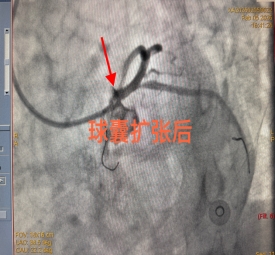

手术台上,每一个操作都精准无误,每一步决策都果断坚定。在生死竞速的关键时刻,心血管内科三病区杨金勇副主任团队默契配合、沉着应战,凭借精湛的技术成功为患者实施介入治疗,开通了重度狭窄的血管,恢复了心脏正常供血。整个手术过程十分顺利,患者胸痛症状迅速缓解,生命体征趋于平稳,成功脱离生命危险,目前已顺利出院。